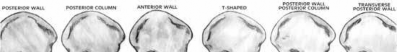

Which of the following associated type acetabular fracture patterns is defined based on the fact that all articular segments are detached from the intact portion of the ilium, which remains attached to the sacrum through the sacroiliac joint?

There are 5 simple and 5 associated fracture types according to the classification system created by Judet and Letournel. The key feature which distinguishes both column fractures from other associated types is that all articular segments are detached from the intact portion of the ilium, which remains attached to the sacrum through the SI joint.

Although the transverse plus posterior wall, T-shaped, and anterior plus posterior hemi-transverse fractures all show involvement of the anterior and posterior columns, they are not “both columns” because a portion of the

articular surface remains in its normal position, attached to intact ilium.

The intact ilium is responsible for the "spur sign" noted most prominently on the obturator oblique radiograph.

Illustration A demonstrates the 10 types of acetabular fractures as created by Judet and Letournel. Illustration B is an example of a both column acetabular fractures as seen on the obturator oblique radiograph.